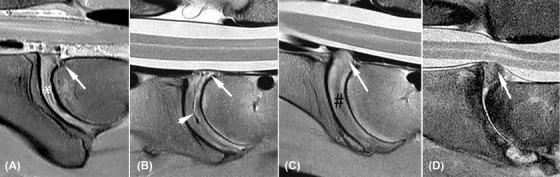

[Magnetic resonance imaging of diseased cervical and lumbar intervertebral discs].

Neurol Med Chir (Tokyo). 1989 Feb;29(2):99-105. doi: 10.2176/nmc.29.99.